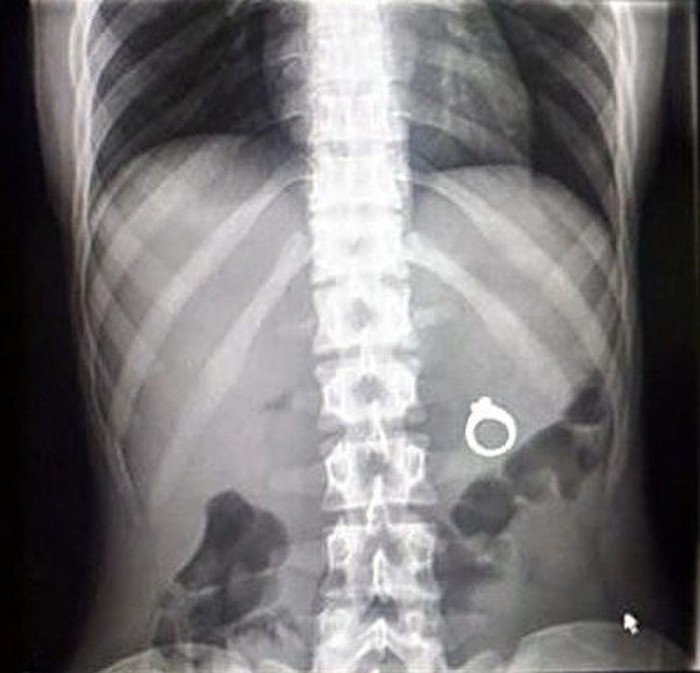

Jakarta - Pemindai sinar X salah satu alat medis yang memudahkan untuk melihat dalam tubuh. Namun ternyata banyak hasil yang aneh mulai dari jepitan rambut hingga cincin.

Cincinnya kok malah ditelan ya? (Foto: Brightside)